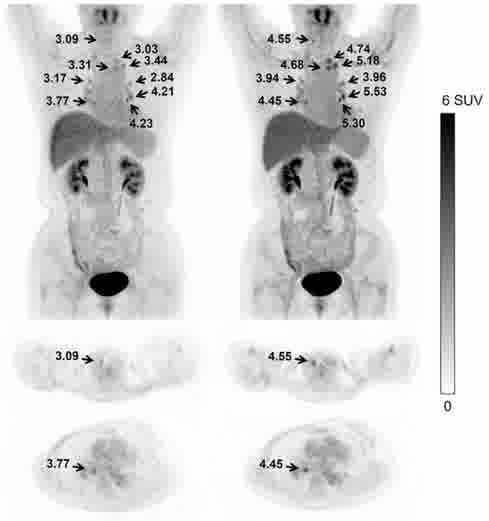

超低计数68Ga三符合重建

传统算法 改进的算法 双符合重建68Ga和18F混合的信号 三符合重建仅含68Ga的信号 传统算法 改进的算法 缺角度系统